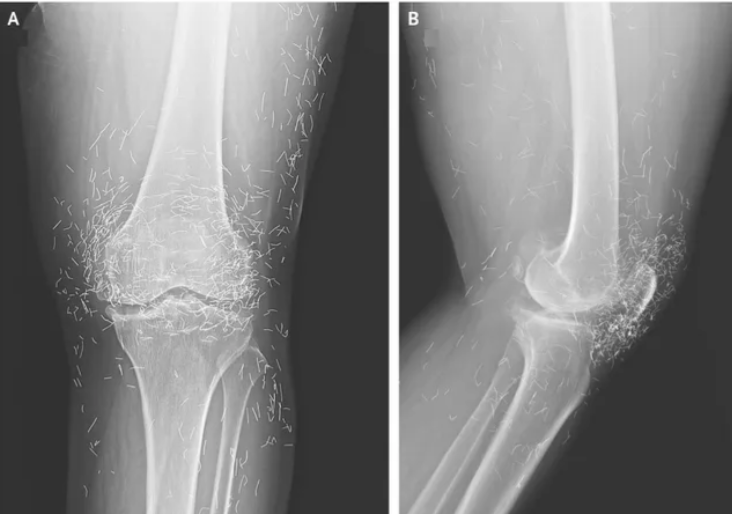

توجهت امرأة تعاني من ألم شديد في مفاصل ركبتيها إلى المستشفى في محاولة لمعرفة سبب آلامها المزمنة فأظهرت الأشعة السينية مئات الخيوط الذهبية الموجودة داخل ركبتها وفق ما ذكره تقرير لموقع “ساينس ديلي” .

وحين ازدادت وتيرة الألم ذهبت إلى المستشفى، فكشفت الأشعة السينية لركبتها اليسرى أن عظم الساق في الجزء الداخلي من المفصل قد ازداد سمكًا وصلابة. كما وُجدت نتوءات عظمية، على الأجزاء الداخلية من عظم الساق وعظم الفخذ بجوار مفصل الركبة.

ولكن الأهم هو ملاحظة الأطباء لمئات البقع في الأشعة السينية حول مفصل الركبة، والتي تبيّن أنها خيوط ذهبية صغيرة. وقال التقرير أن استنتاج الأطباء كان أن الخيوط قد أُدخلت كجزء من علاجات الوخز بالإبر للمرأة. وقد تُركت هذه الخيوط الذهبية القصيرة والمعقمة عمدًا في الأنسجة لتوفير تحفيز مستمر. وحذر التقرير من أن ترك الخيوط في مكانها ليس خاليًا من المخاطر، فقد أدى إلى تكوّن أكياس في حالات سابقة.

كما يمكن أن تنتقل الخيوط داخل الجسم، وقد تُلحق شظاياها الضرر بالأنسجة المجاورة. على سبيل المثال، انتقلت خيوط الذهب التي غُرست في ظهر امرأة كورية جنوبية تبلغ من العمر 75 عامًا إلى أسفل ساقها اليمنى على مدى 10 سنوات، مما تسبب في التهاب النسيج الخلوي – وهو عدوى جلدية عميقة.

وقال الأطباء أنه لا يوجد دليل على فعالية هذه الممارسة، وتشير بعض الحالات إلى أنها قد تُفاقم التهاب المفاصل بشكل غير مباشر من خلال منع المرضى من الحصول على العلاج المناسب في الوقت المناسب.